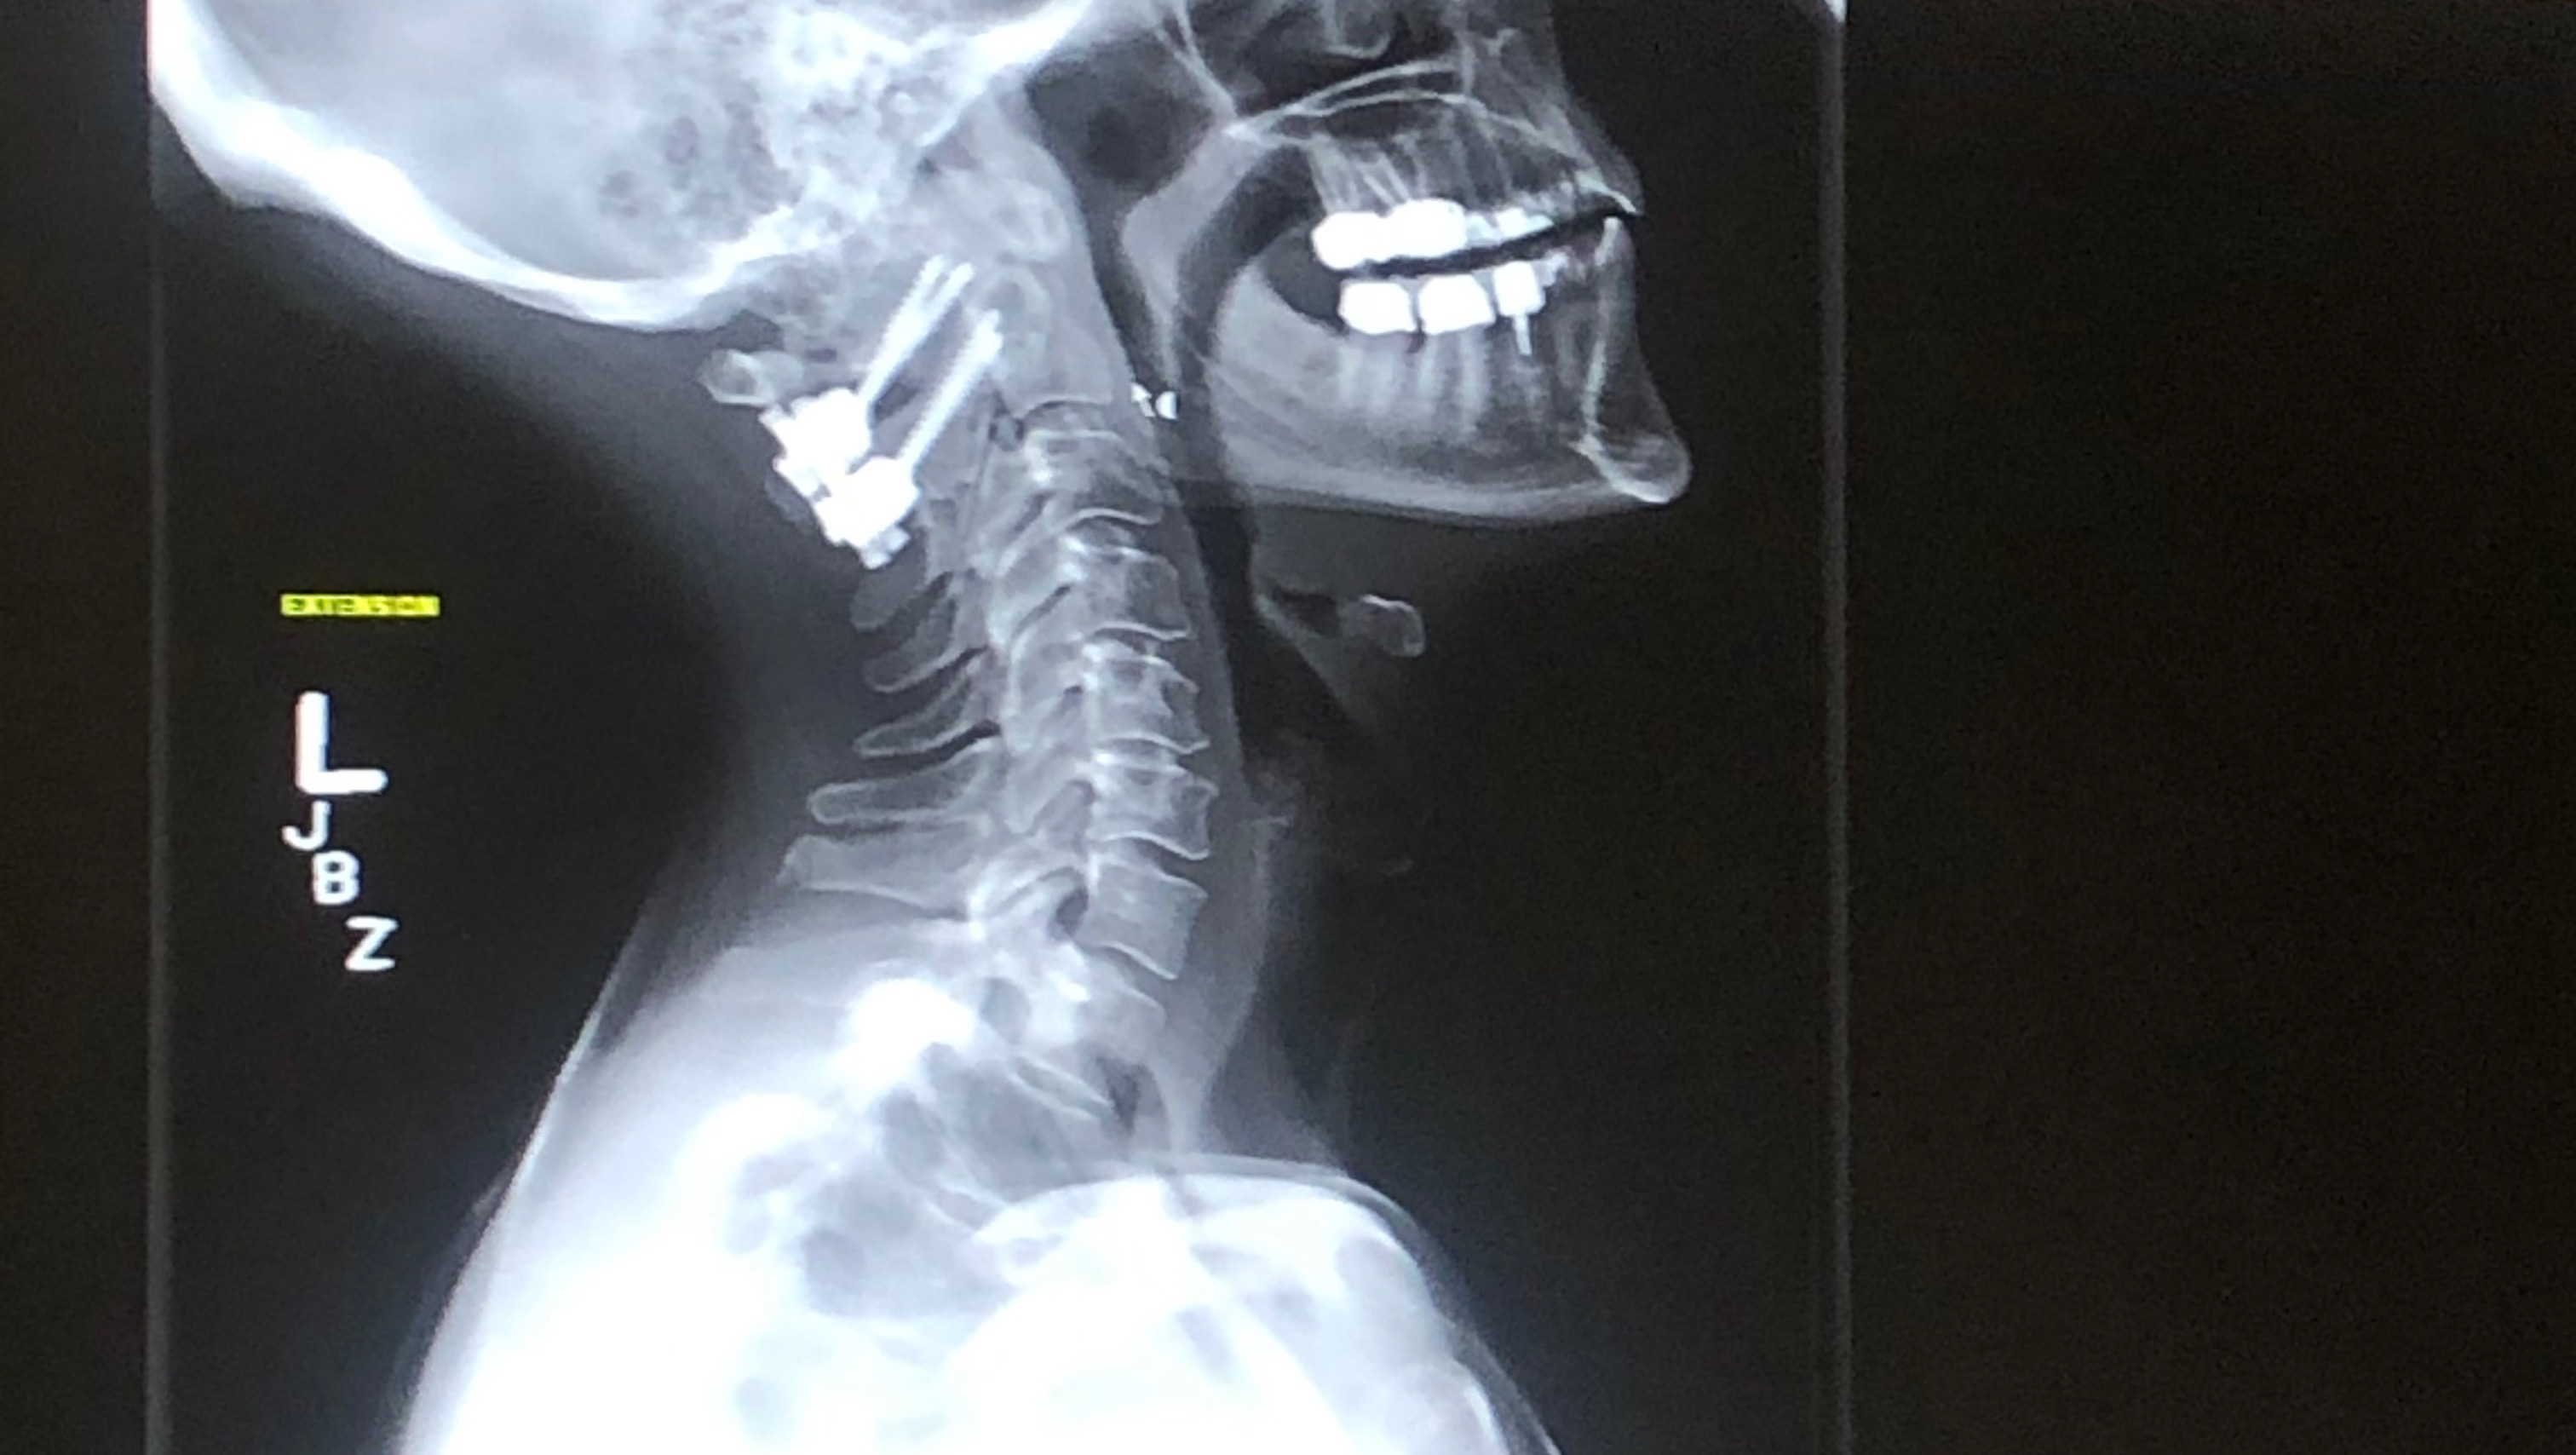

In 2019, I broke my neck. As I headed into surgery to repair my shattered C1, I never thought I’d walk again, let alone hike.

For three long months, I wore a hard plastic brace, struggled to regain movement, and navigated life with a bunch of hardware drilled into my neck.